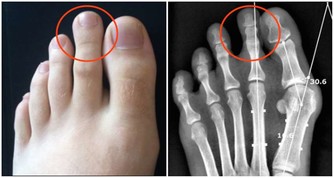

人體內濕氣重會引發許多的疾病,人也會感覺身體沉重、面色發黃、精神狀態不佳!

然而,因為我們現代人吃肉較多、運動量又較小,因此,大部分人體內都有濕毒!